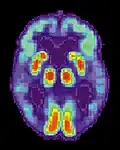

- Tomografia cu Emisiune de Pozitroni - PET

- Prin efectuarea unei Tomografii cu Emisiune de Pozitroni (PET), folosind molecule de glucoză marcate cu Fluor-18 (izotop radioactiv), se constată o reducere a utilizării glucozei (singurul element nutritiv al creierului), un așa zis "hipometabolism al glucozei", în special în regiunile frontale și parietale, în comparație cu persoanele normale.

Tomografie cu Emisiune de Positroni-PET . Imagini caracteristice la un pacient cu boala Alzheimer.